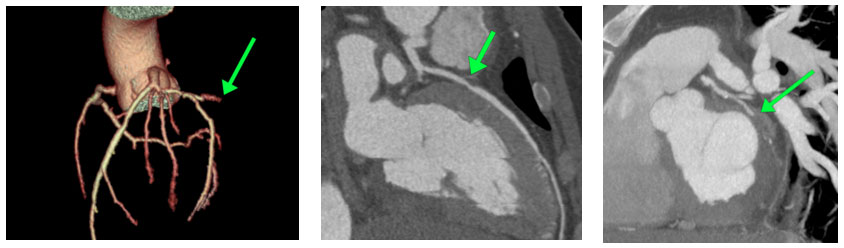

Heart Artery Blockage in a 40-Year-Old Runner

A long-distance runner came to the emergency department with sudden chest pain. Blood tests showed elevated troponin, a marker of heart injury, with no other significant medical/family history. Coronary CT angiography revealed a severe (70%) narrowing in the left anterior descending artery and a complete blockage in the left circumflex artery. The patient immediately underwent stent placement by the cardiologist, restoring normal blood flow and thus averting a life‑threatening situation.